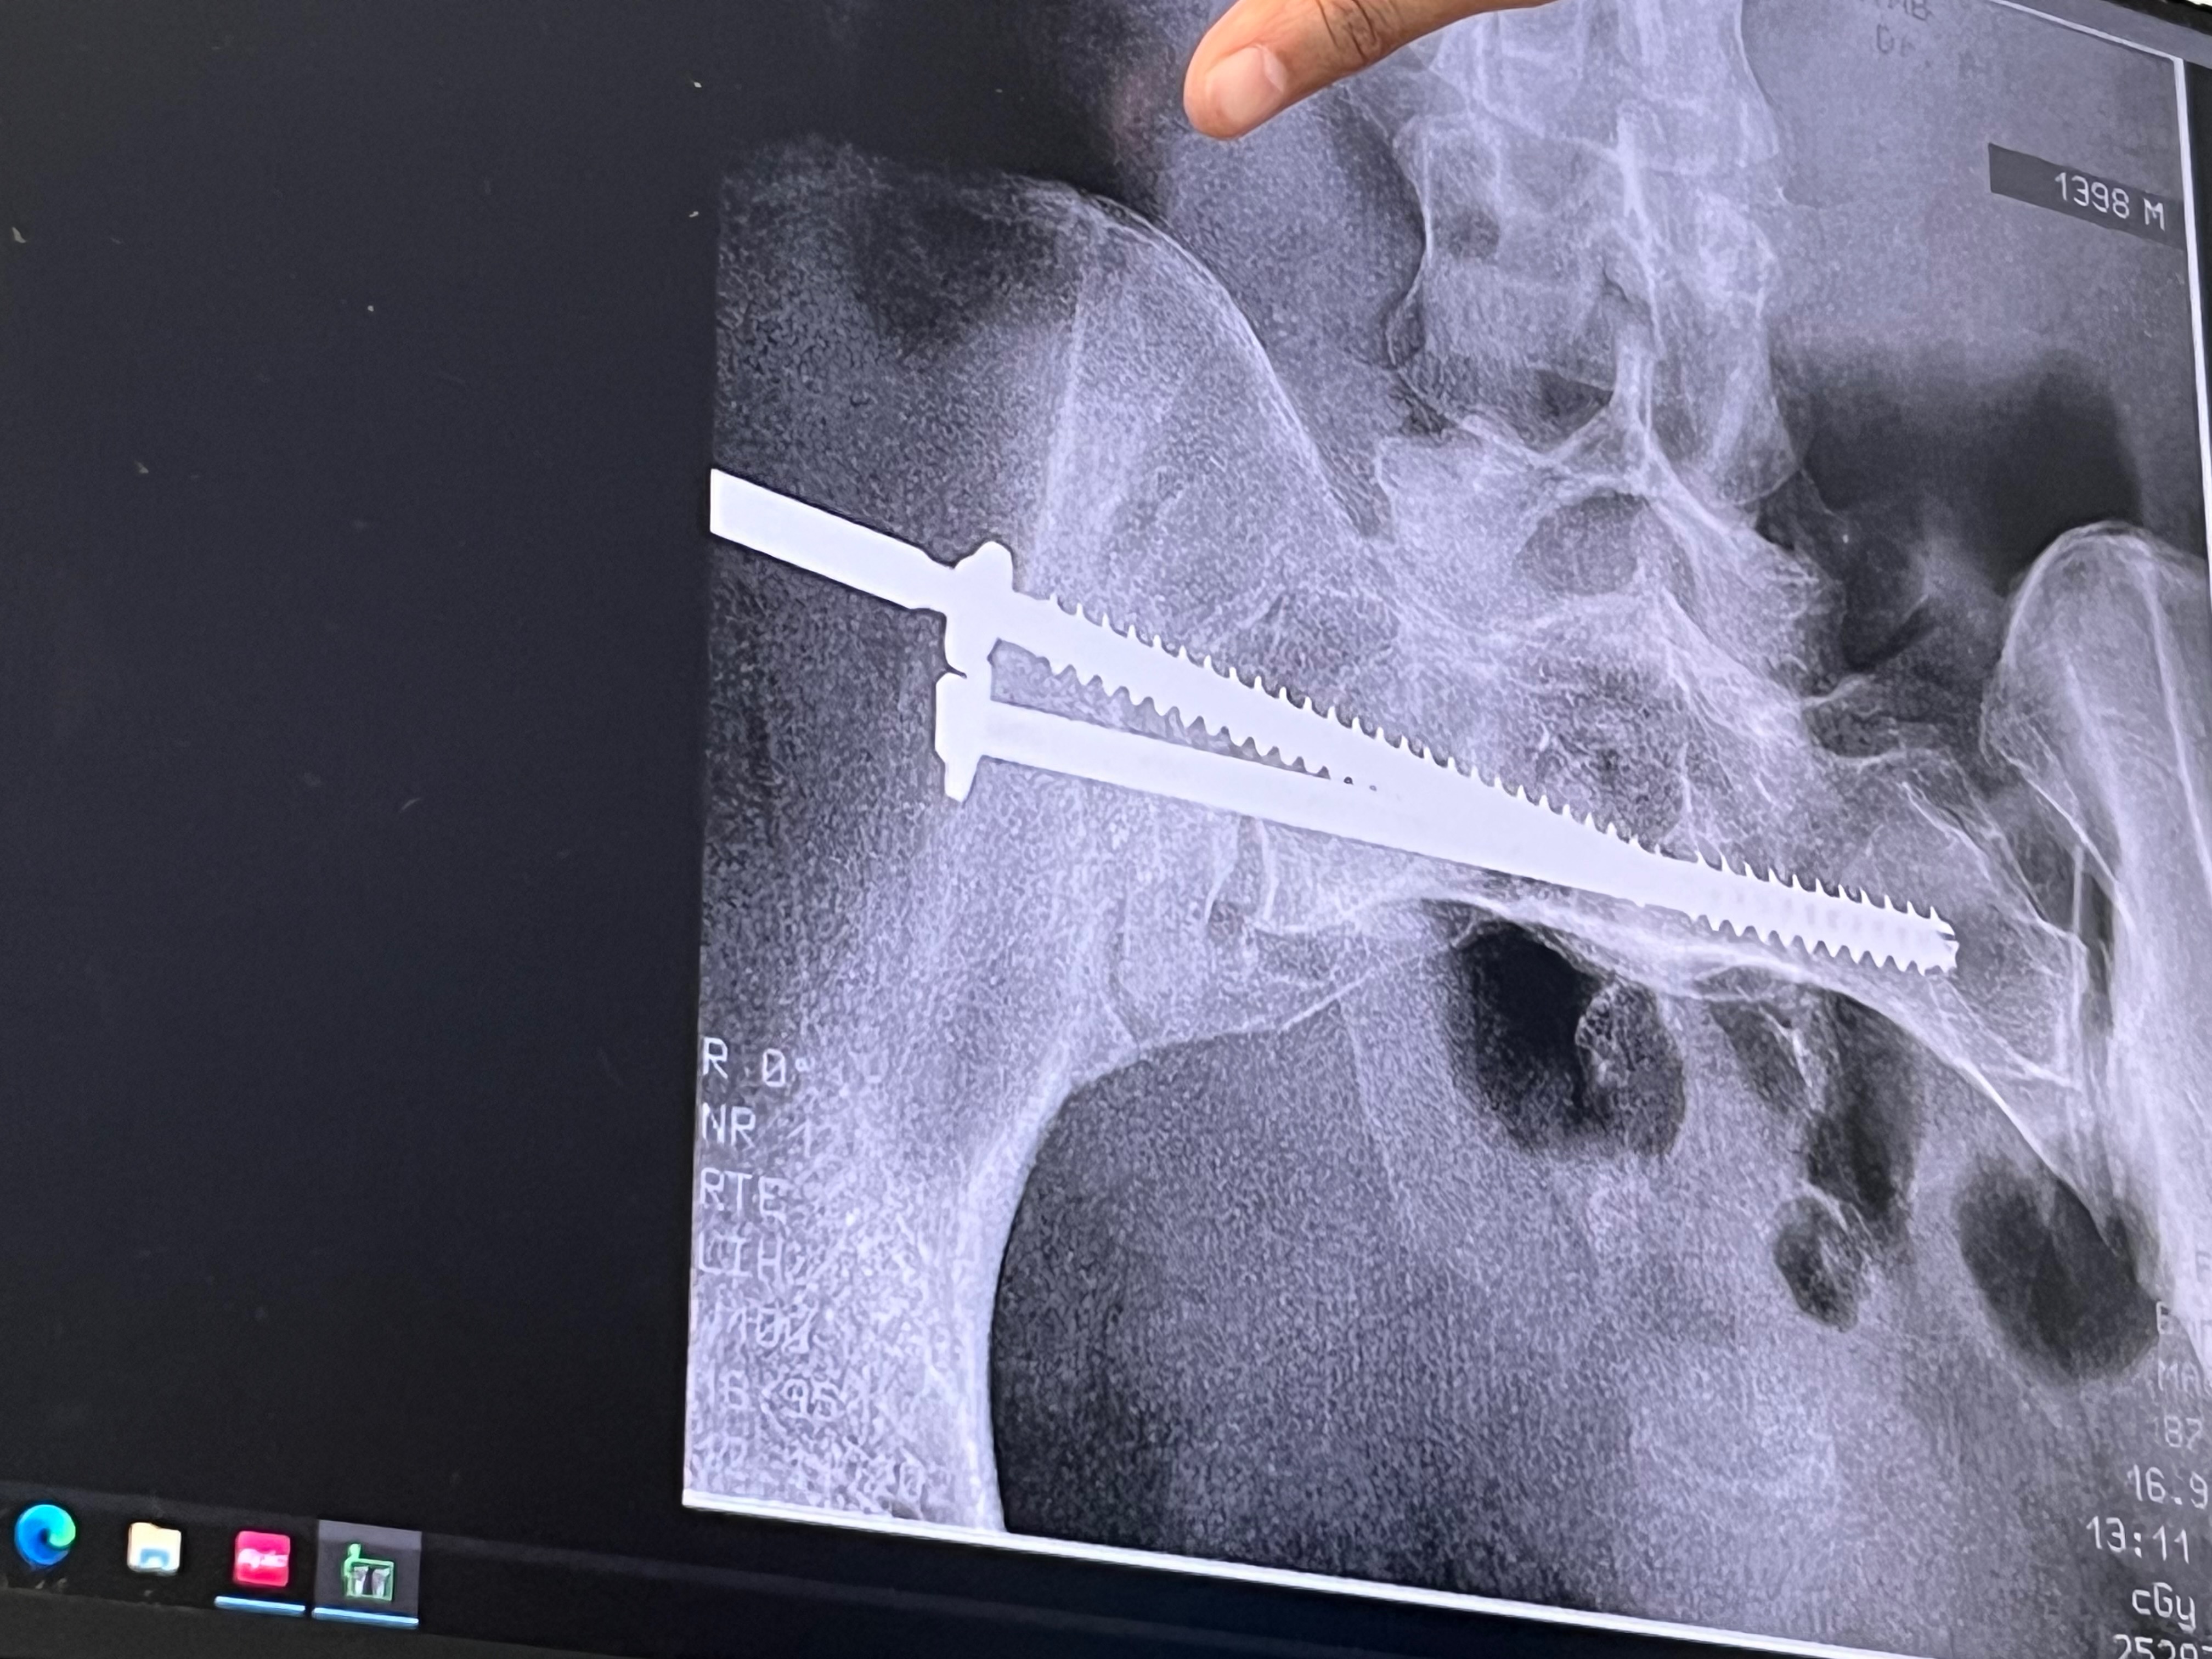

On Dec 9th at approximately 8am, my daughter was involved in a vehicle hit and run. She got out of her car on the Kemah bridge because she had a flat tire. The next thing she remembers is coming to about 40 feet from her car, a 2018 Red Jeep Renegade. Her phone and shoe were in the middle of the bridge. The car that hit her never stopped to render aid. She got up and remembers dragging her right leg to get her phone to call for help. As people were passing her and she was screaming, crying, and waving passing cars down for help, no one stopped to help her. Someone, however, did contact 911, letting them know there was a bleeding woman on the Kemah bridge. EMS showed up and debated life-flighting her to UTMB but chose to just rush her by EMS instead of waiting. She has a broken left foot, a fractured left knee, a broken left ankle, a broken right pelvic bone, 5 staples in her head, 3 spots fractured on her spine, and a contusion on her brain. She will lose the skin between her knee and ankle, needing skin grafts as healing happens. She is stable, but we have a long way to go. She has had 8 surgery's. She will be in the hospital through Christmas and possibly even New Year's. She has four beautiful girls and several family members praying for her. We ask that if you know anything about her accident, please reach out to Detective McGee with the Seabrook Police Department. Please continue to pray for Kristie and her girls and our family.